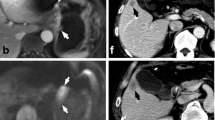

Some examples of DCE-MRI in GC are shown in Figs. 2, 3 and 4.

DCE-MRI showing a tumour of the gastric antrum (a) in a 73-year-old male. The Ktrans (b) was 0.279 min−1, the Kep (c) was 0.605 min−1 and the Ve (d) was 0.482. Final pathology (e): diffuse type (Lauren classification), staged as pT4aN3. DCE-MRI of a tumour of the gastro-oesophageal junction (Siewert III) (f) in a 68-year-old male. The Ktrans (g) was 0.117 min−1, the Kep (h) was 0.461 min−1 and the Ve (i) was 0.253. Final pathology (j): mixed type (Lauren classification), staged as pT3N1. DCE-MRI of a tumour of the gastric antrum (k) in a 49-year-old male. The Ktrans (l) was 0.016 min−1, the Kep (m) was 0.575 min−1 and the Ve (n) was 0.029. Final pathology (o): intestinal type (Lauren classification), staged as pT4aN2